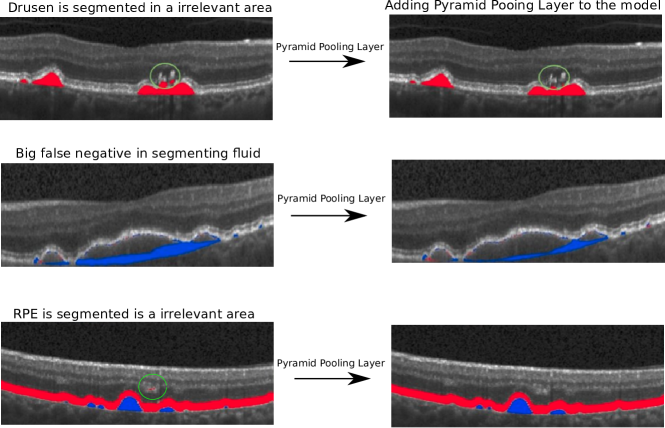

Refer to caption

Figure 3: (Left) Output of the basic U-Net [3] and (Right) output of the proposed model. First row: The basic U-Net has erroneously segmented the drusen as the bright areas above RPE, although there should be no drusen on top of the RPE. Second row (blue is false-negative drusen): in the basic U-Net’s output, drusen region exceeds the network’s receptive field. Third row (drusen in blue and RPE in red): The part of the image which is completely outside of the outer retina is segmented as RPE by the basic U-Net.

An example of segmentation output is shown in Fig. 3. It shows how the pyramid pooling method solves some fundamental issues in drusen segmentation by adding global contextual information to the feature maps which are being transferred through the network. We quantitatively evaluated the segmentation performance of the drusen, OBRPE and BM segmentation. Table 1 shows the results of this evaluation, per patient dice coefficient for drusen segmentation and mean absolute error for OBRPE and BM. In addition, figure 4 shows a box-plot of per patient dice coefficient for drusen and mean absolute error for BM and RPE segmentation. One can observe that by using the pyramid module, our proposed method was able to outperform the other baseline networks.